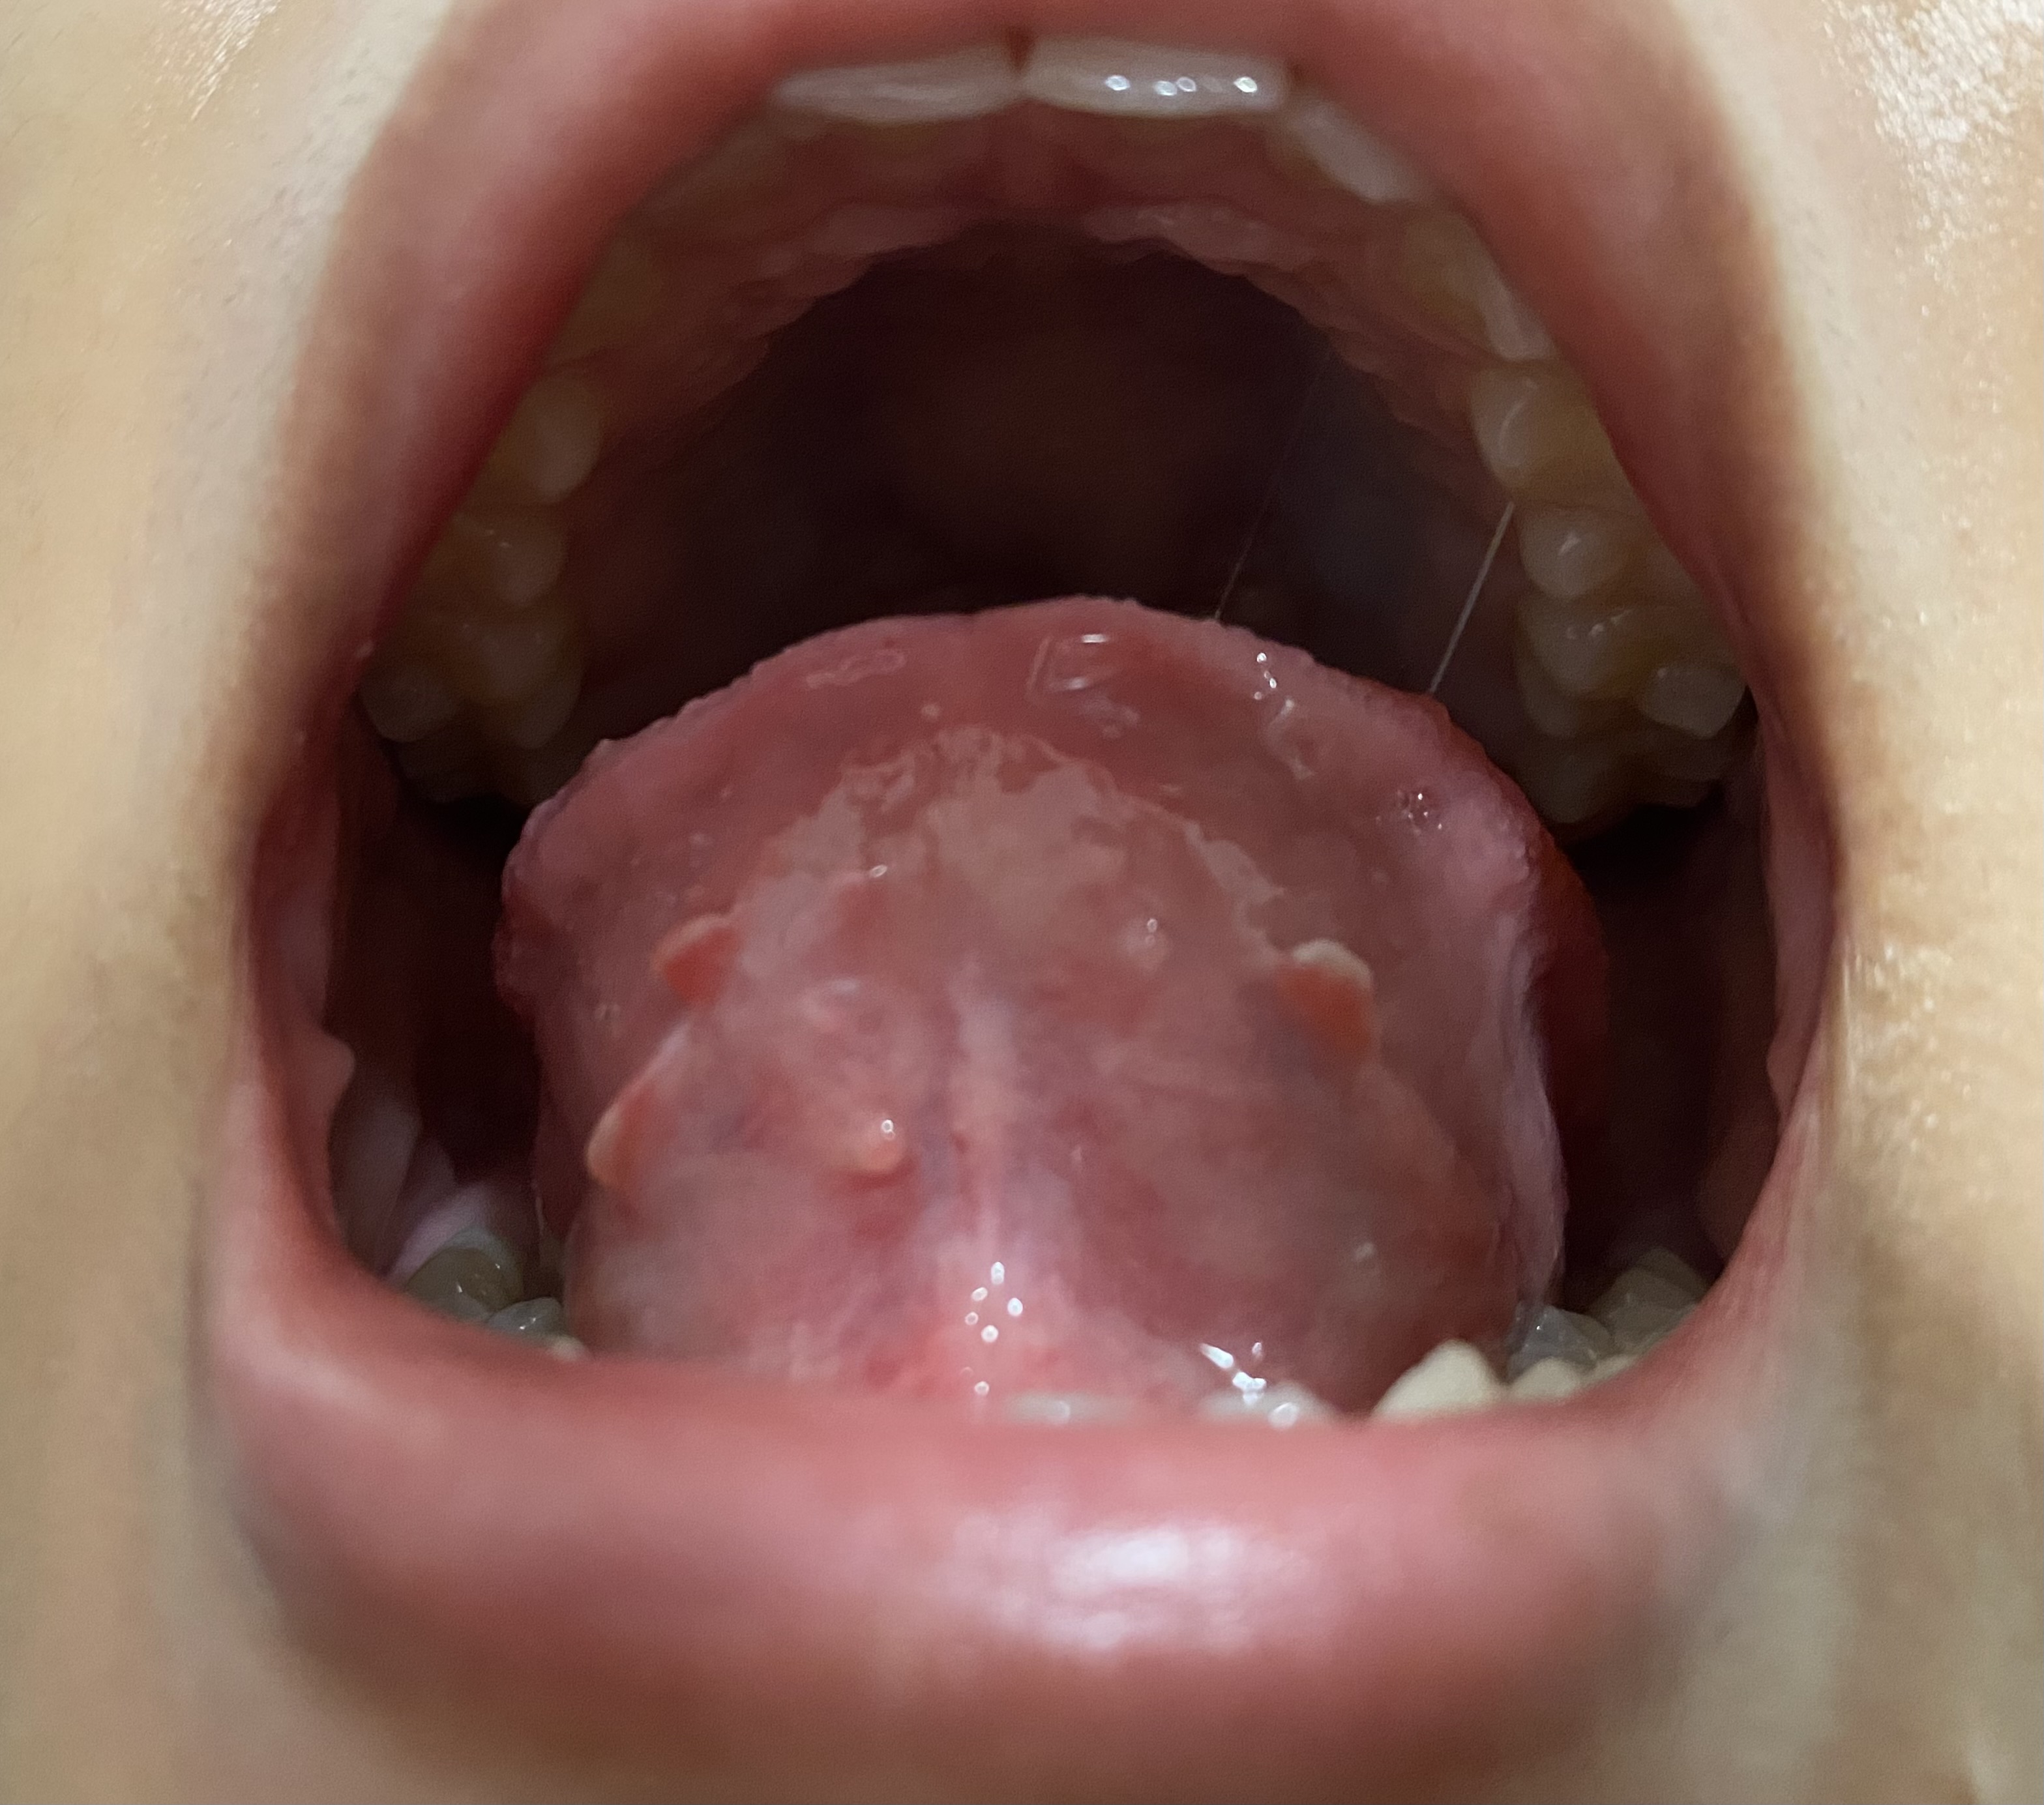

https://haamor.com/media/create_topic/20250420213703.jpeg

ช่วงนี้รู้สึกแปรงฟันแล้วแสบปากมากๆเลยค่ะ แสบจนน้ำตาไหลเลยก็มี แปรงฟันเลือดออกทุกครั้งเลยด้วยค่ะ กินผลไม้พวกสตอเบอรี่ก็แสบค่ะ ตอนไม่ได้กินอะไรก็รู้สึกเจ็บๆอยู่นิดหน่อยค่ะ พอมาลองส่องดูแล้วเจอเหมือนเนื้อๆงอกออกมาแบบในรูปเลยอะค่ะคุณหมอ อยากทราบว่ามันเกิดจากอะไรได้บ้าง แล้วต้องรักษายังไงได้บ้างคะ

ติ่งงอกที่เห็นเป็นปกติครับ

แต่ใต้ลิ้นมีฝ้าขาวผิวอักเสบ อาจเกิดจากแพ้อาหารหรือขาดวิตามิน เบื้องต้นลองใช้ kamillosan M พ่นวันละสามครั้งครับ ถ้าเจ็ดวันแล้วยังไม่ดีขึ้นให้ไปพบแพทย์หูคอจมูกครับ